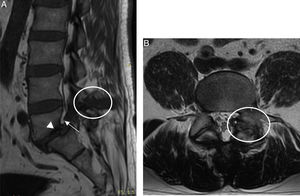

Clinical caseA 44-year-old male, attending hospital due to low back pain. One year earlier he experienced onset of progressive low back pain irradiating to the left pelvic limb. Six months earlier he presented sudden onset left knee arthritis, which remitted with anti-inflammatory drugs. The patient was hospitalised, physical examination found independent gait, guarding, claudication, decreased spinal mobility due to pain, positive Lasègue and Bragard, hypoaesthesia in L5-S1 dermatome, and RI with joint effusion. Blood biometry, urinalysis, erythrocyte sedimentation rate and C-reactive protein with normal parameters, serum uric acid of 11.8mg/dl and uric acid in 24h urine test: 560mg. X-ray with lytic spondylolisthesis of L5, on magnetic resonance imaging (MRI) hypointense signal in T1 and heterogeneous in T2 located in the L4-L5 interspinous space, and in the left facet joint invading the neuroforamen with bilateral lysis of the interarticular pars (Fig. 1). Ultrasound of the left knee showed “double contour” of the cartilage of the medial femoral condyle (Fig. 2A) and thick-walled Baker's cyst with hyperechoic stippling in its interior (Fig. 2B). Laminectomy, L5 radicular release, L5-S1 transpedicular fixation and postero-lateral arthrodesis. The histopathological study of the material removed by surgery reported amorphous amphophilic acellular material comprising epithelioid histiocytes fusing their cytoplasms together to form foreign body multinucleated giant cells (Fig. 2C).

MRI lumbosacral spine (A) Sagittal plane in T1 with hypointense image in L4-L5 interspinous space (circle) invading the neuroforamen (arrow) and spondylolisthesis of L5 (arrow head). (B) Axial plane in T2 with heterogeneous image in left facet joint with bilateral lysis of the interarticular pars (circle).